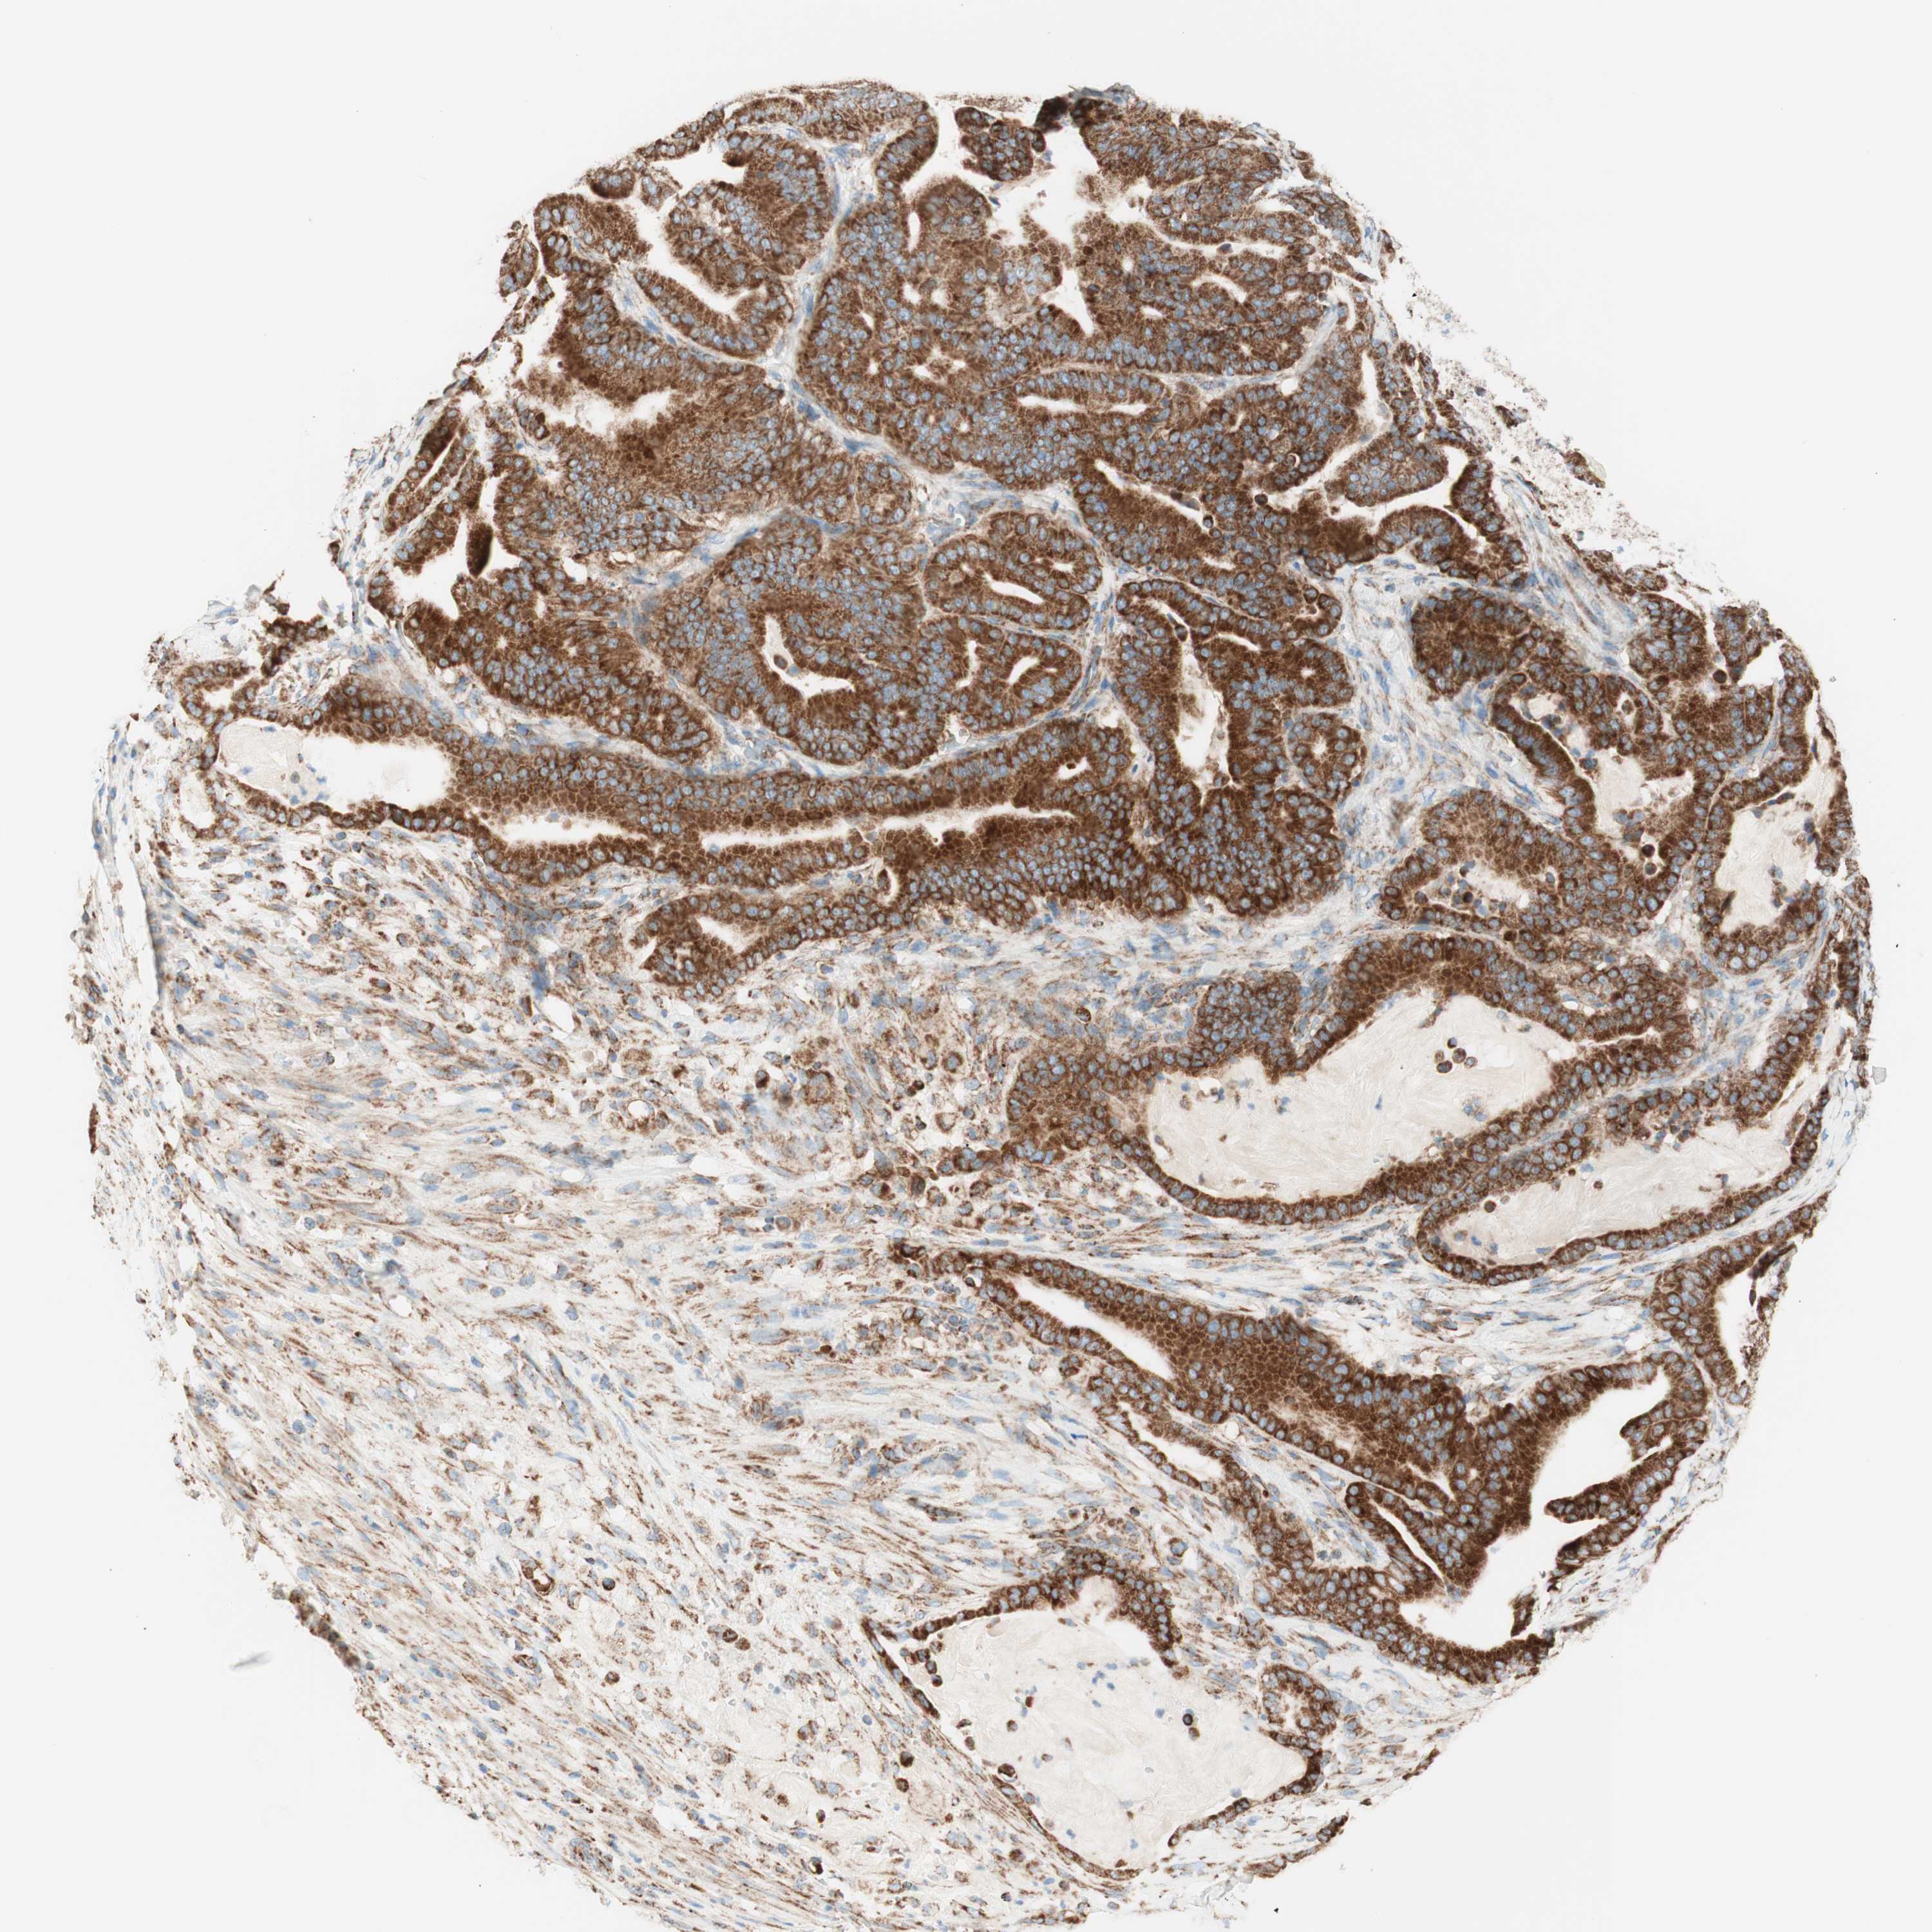

PANCREATIC CANCER - Protein expressioni

A mouse-over function shows sample information and annotation data. Click on an image to view it in a full screen mode. Samples can be filtered based on level of antibody staining by selecting one or several of the following categories: high, medium, low and not detected. The assay and annotation is described here.

Note that samples used for immunohistochemistry by the Human Protein Atlas do not correspond to samples in the TCGA dataset.

Antibody stainingi

Antibody staining in the annotated cell types in the current human tissue is reported as not detected, low, medium, or high, based on conventional immunohistochemistry profiling in selected tissues. This score is based on the combination of the staining intensity and fraction of stained cells.

Each image is clickable and will lead to virtual microscopy that enables deeper exploration of all samples and also displays staining intensity scores, fraction scores and subcellular localization as well as patient and tissue information for each sample.

Antibody HPA011562

Antibody CAB005585

Staining

High

Medium

Low

Not detected

Intensity

Strong

Moderate

Weak

Negative

Quantity

>75%

75%-25%

<25%

None

Location

Nuclear

Cytoplasmic/membranous

Cytoplasmic/membranous,nuclear

Adenocarcinoma, NOS

Adenocarcinoma, metastatic, NOS